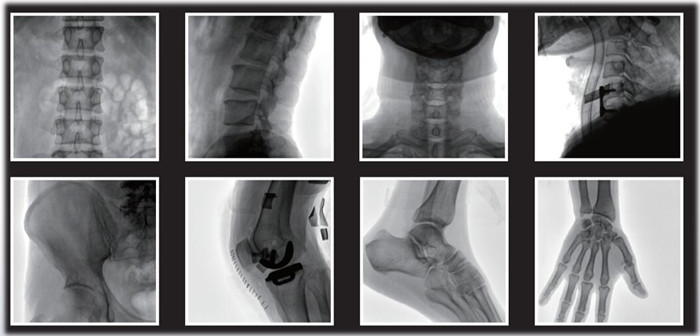

1)小C,骨科手術(shù)必備設(shè)備,也被稱為骨科小C。作為骨科醫(yī)生的眼睛,能在手術(shù)中透視實(shí)現(xiàn)準(zhǔn)確定位,輔助醫(yī)生順利、快速、高效完成手術(shù)。目前,小C在我國(guó)普及率極高,基本上所有二級(jí)及以上醫(yī)院都標(biāo)配小C。

小C在骨科的應(yīng)用是全方位的